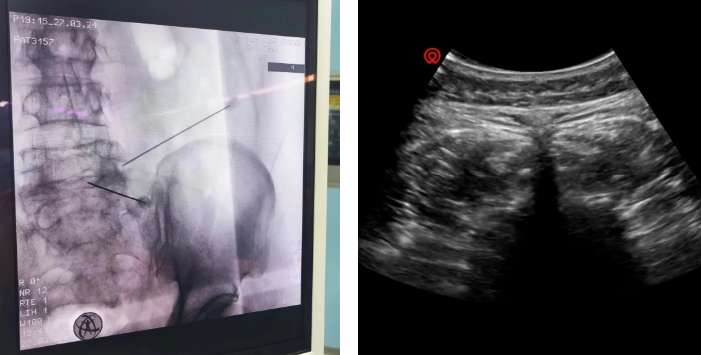

后来经人推荐,李大爷来到了星城院区疼痛科,崔继东主任详细了解李大爷病史后,为他安排了脉冲射频治疗。经过1小时治疗后,李大爷感到疼痛明显缓解,以前的症状消失了90%以上,当天夜里就睡得比较好,这也是他近一个月来第一次能睡个好觉。通过回访,李大爷的疼痛最近未再复发。

脉冲射频治疗是通过射频能量对病毒侵犯的神经根进行调节治疗的方法。对神经调控进行电刺激调节,降低神经感觉纤维兴奋性达到减轻痛感的效果,不损害神经。与传统治疗方法相比,脉冲射频具有快速缓解疼痛和降低复发率的优势。

脉冲射频产生热能,对神经纤维进行电刺激及热传导。可以抑制疱疹病毒的活性,减少疱疹的扩散,并促进患者神经纤维的恢复。这种治疗方法不仅快速有效,而且效果持久,可以提供更长时间的疼痛缓解。